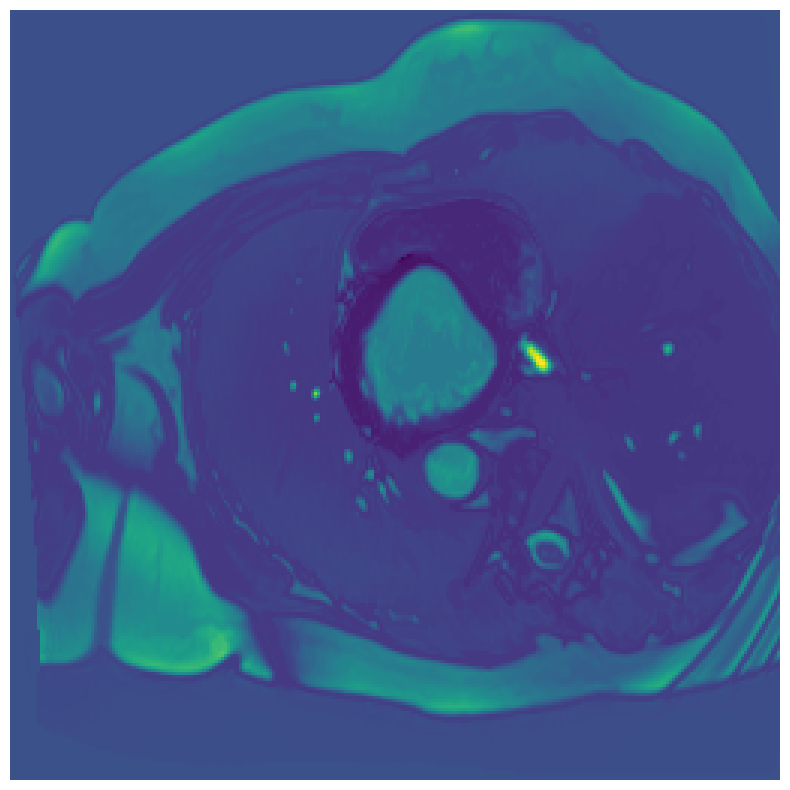

Generally, given an exact, full annotation of an object, such a Euclidean signed distance map encodes also information on the shape of an object. But when using a weak ground truth , where and , inferring a correct extent and shape of the objects is nontrivial. As shown in 1(b), Euclidean distance calculated from a point label source grows radially, regardless of the actual shape of the object, and thus makes little sense from an information point of view. Under the assumption of intra-object homogeneity and inter-object contrast (w.r.t intensities), this problem can be circumvented to a degree by using a distance function that takes also intensity values into account. An example of a commonly used distance measure with an intensity component is the Geodesic distance ([34]). Let denote a path between , with and being neighbors under a chosen adjacency relation. Reusing the notation from before, a Geodesic distance map from the boundary of the ground truth class , , can be defined as

Both the Intensity and the Minimum barrier distance are defined exclusively on the image intensity space. However, from the examples of distance map in 1(d), we can notice that the values still increase somewhat radially from the annotation. This behaviour is similar to the one of the Geodesic distance in 1(c) (which actually includes the spatial proximity in its definition), and is due to the summing operator in the general Geodesic distance definition in Equation 3. While the intensities of two neighboring pixels on a path may be the same, that will rarely be the case in real life, noise riddled images. This makes the Intensity distance function approximately monotonically increasing with increasing length of the path (in space), even on paths where the intensity is mildly fluctuating (e.g. consider a path with even pixels intensity value of and odd pixels intensity value of ). One could thus argue that such a definition of a distance, despite being based exclusively on intensities, is still capable of loosely encoding the spatial distance information.

On the other hand, while we can see that the MBD based maps are similar to Geodesic and Intensity ones (1(e)) with respect to the object shape recovery, they have a less pronounced and smooth increase in the values outward from the source point.

In contrast to Euclidean distance, the Geodesic, Intensity and Minimum barrier distance maps all encode contrast sensitivity and preserve the object structures by harnessing the intensity information of the underlying image. This holds even when calculated from point sources. In practice, using such maps for network training could mean a lower penalty for false positives that occur farther from the point annotation but are close to it in intensity. Thus still enabling the propagation of a sort of shape information (as it can be inferred from the raw image intensities).